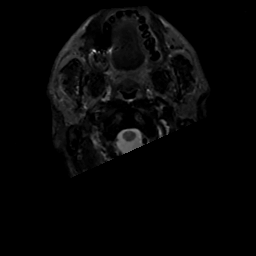

MR Study #3, February 24, 1991 -- Slice #0

[Home][Help][Clinical][Tour 1][Tour 2] Slice 0